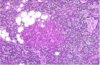

Islet Cell Tumor

Islet Cell Tumor

Insulinoma (Islet Cell Tumor)

Islet Cell Tumors